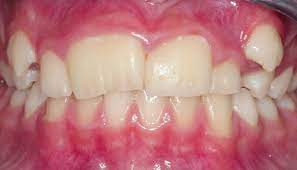

- 2. Hypomaturation:

- Enamel of normal thickness but wears away easily